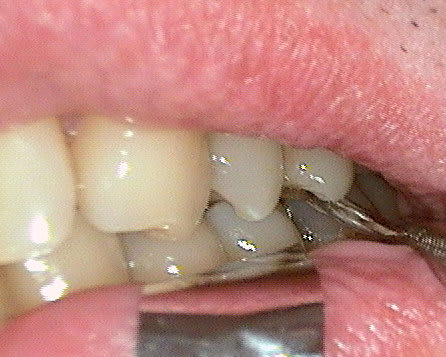

Un patient de 52 ans présente une fracture de racine au site 26.Après division de la racine, extraction de la dent,préparation de la cavité avec un foret conique triangulaire (3 faces,condensation de l´os), puis implantation à 50 Ncm (implant 10mm long, 4,5mm diamètre).Utilisation d´acide hyaluronique pour stimuler la synthèse des ostéoblastes.Pose d´un clip gingival pour préformer la gencive.Après 7 semaines, réalisation d´une empreinte fermée en 5 minutes.Une semaine après, fixation de la couronne définitive ( on observe déjà une ostéointégration).

Pour laisser entrevoir la technique MIMI (Minimale Invasive Method Implantation) développée par le Dr Armin Nedjat voilà la séquence en photos et radios d'un cas d'extraction implantation immédiate technique simplifiée.

Bonjour je connais bien les techniques du Dr Nedjat pour les pratiquer depuis de nombreuses années. Il me demande de l'aider un peu vu la barriere de la langue pour la réponse aux questions.. On voit sur une radio que passer dans le septum impose de faire un "summers modifié", du type carote osseuse condensée à l'osteotome pour preparer un lit implantaire dans ce cas on peu placer un 8mm en base large et avoir un pilier dans l'axe. OK. Ca n'a pas été son choix car il developpe en Allemagne depuis 15 ans sa technique dite MIMI (voir mon post précédent) qui consiste a fraire une osteotomie avec des expanseurs suite à un forage minimal pour obtenir une stabilité primaire tres élevée la plupart du temps 60/70N..Cette technique est tres répandue en Allemagne, plus de 3000 confreres l'utilisent avec un systeme monobloc ou deux pieces..je vais poster dans les jours qui viennent sufisament d'infos pour que vous puissiez vous faire une idée, j'ai des dizaines de cas iconographiés de A à Z. Dans ce cas oui c'est un 4,5mm, l'implant est posé avec son "shuttle" partie intermédaire porte implant laissé intra muqueux et qui "encaisse" le couple de serrage important de la pose. Dessus est clipsé un "gingiva clips" qui est un conformateur gingival laissé pour la cicatrisation. L'empreinte se fait en laissant Shuttle et gingiva clips. Le shuttle est déposé pour la mise du pilier. Il y a toute une technique ..description à venir et cas cliniques aussi ..A suivre..